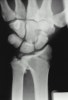

X-ray : 요수근 탈구(Radiocarpal dislocation)

요수근 관절(Radiocarpal joint)에서 탈구가 일어나는데 근위 수근열(Proximal carpal row) 자체의 인대 손상을 동반할 수도 있으며, 요골 경상돌기의 골절을 동반할 수 있는 고에너지에 의한 매우 드문 손상입니다.

탈구에 의해 수장측의 요주상유두 인대, 장 요월상 인대 및 단 요월상 인대와 후방으로 후방 요수근 인대가 파열될 수 있습니다.